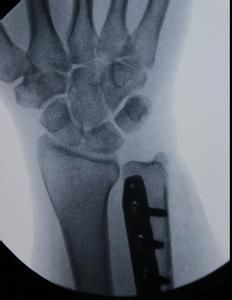

(4)腕部X光攝片大多數可見尺骨相對於撓骨長出2mm以上